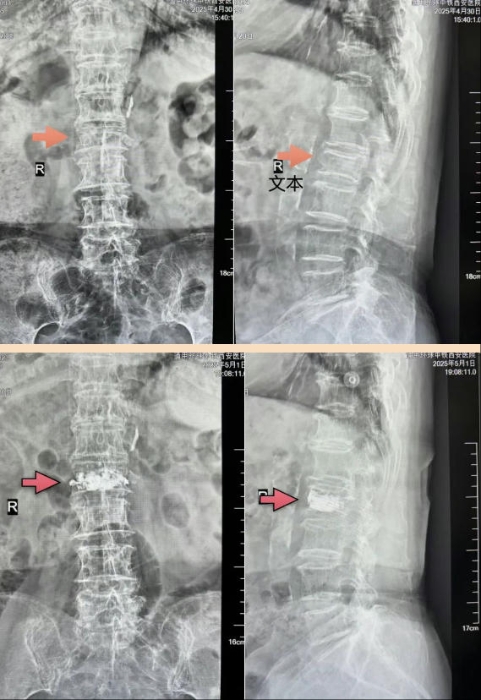

姬主任仔细评估后,决定为老人实施骨水泥微创手术。这种手术具有创口小、恢复快的特点,可让申奶奶免于繁琐的开放手术,减轻痛苦。

术前与心血管内科、麻醉科联合制定多套应急预案,术中,医生们谨慎而细致的操作,让申奶奶感受到了专业医疗与人性关怀的结合。术后,老人疼痛明显缓解,身体状况也稳定下来。医护人员细致入微的关怀,更让这位老人备受温暖。